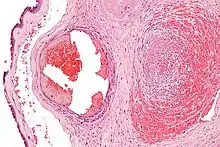

Excessive generation of fibrin due to activation of the coagulation cascade leads to thrombosis, the blockage of a vessel by an agglutination of red blood cells, platelets, polymerized fibrin and other components. Ineffective generation or premature lysis of fibrin increases the likelihood of a hemorrhage.